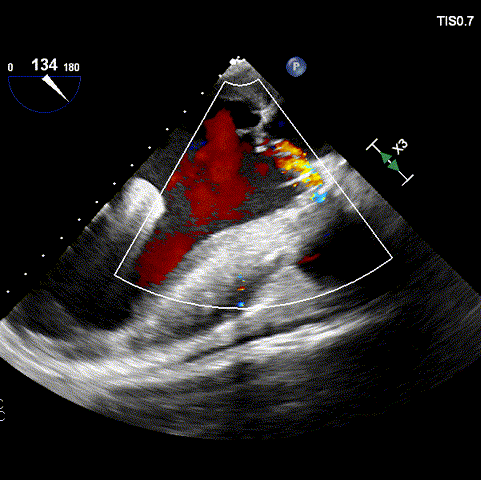

在导丝跨瓣及调整角度过程中,患者出现急性左心衰,TEE观察到患者二尖瓣由术前轻度反流变为重度反流,心电监护提示ST段明显下移,血压下降至不足60mmHg、心率明显加快至130次/分,血氧饱和度下降至88%。考虑出现急性左心衰、循环崩溃,立即将输送系统快速过弓、跨瓣,精准定位后予以快速释放AV31瓣膜脱钩。

术中TEE观察患者重度二尖瓣反流

瓣膜释放后二尖瓣反流明显减少